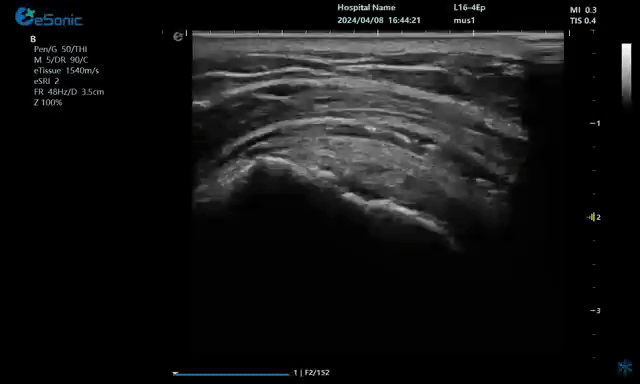

病例:冈上肌肌腱钙化穿刺治疗

640.gif

注射麻醉药

640 (1).gif

注射药物

640 (2).gif

无磁导航技术引导穿刺钙化点

钙化物.jpg

取出的钙化物